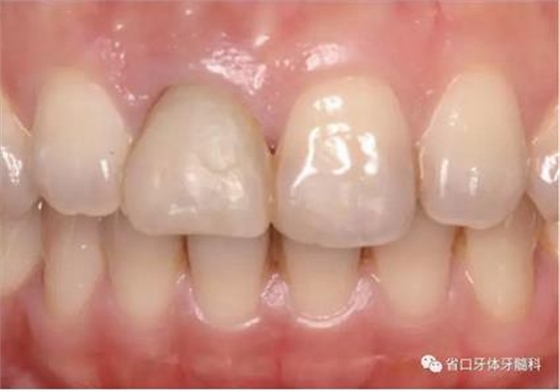

圖1 術(shù)前口內(nèi)照

圖2 術(shù)前口內(nèi)照

圖3 術(shù)前口內(nèi)照

1.?病例簡介 43歲女性患者,主拆:右上前牙松動不適數(shù)日要求修復(fù)。現(xiàn)病史:患者數(shù)年前右上前牙因“齲壞”于外院行根管治療(具體不詳),數(shù)日前牙冠松動不適,現(xiàn)覺影響咀嚼及美觀,遂來我院要求進(jìn)一步診治。否認(rèn)高血壓、心臟病等重大疾病,否認(rèn)結(jié)核、肝炎等傳染病史,否認(rèn)手 術(shù)、輸血史等,未發(fā)現(xiàn)藥物過敏。無吸煙習(xí)慣。臨床檢查:口外觀顏面基 本對稱,皮膚無紅腫破潰,顳下頜關(guān)節(jié)區(qū)無彈響、雜音、壓痛,開口度約 37mm,開口型“↓”,頜下、刻下和頸部未及腫大淋巴結(jié)。中位笑線??趦?nèi)檢查,口腔衛(wèi)生可,色素(+),BOP(-),PD=2mm,上頜右側(cè)中切 牙冠部變色,冠根折斷至齦下3mm,叩不適,松動Ⅱ°~Ⅲ°。牙齦稍紅, 齦緣水平及齦乳頭高度可,屬于中厚齦生物型,附著齦寬度約5mm,唇系帶附著可。上頜右側(cè)中切牙缺牙間隙與對側(cè)同名牙一致,約>7mm,修復(fù)空 間良好。與對頜牙覆合覆蓋正常。MCT檢查示上頜右側(cè)中切牙冠根折斷至骨 下,根管內(nèi)見充填物,根充不全,根尖見陰影,大小約3mm×3mm。牙槽窩根方可用骨量可,唇側(cè)骨壁完整,冠方骨壁厚度約1mm。